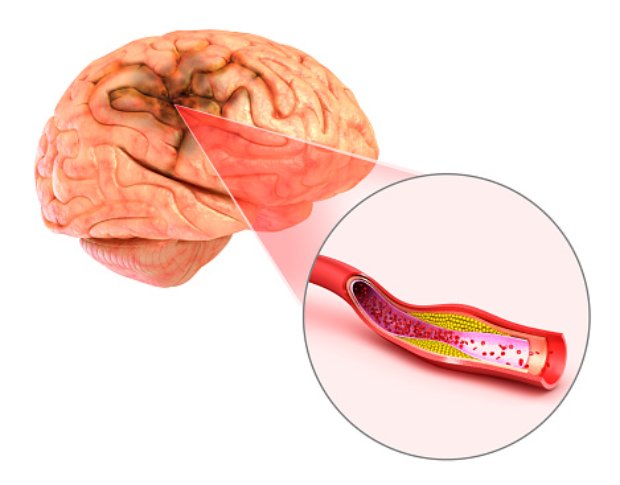

World heart day: Enlarged heart, diabetes and heart disease, fluid around the heart, massive heart attack

September 29th is World Heart Day, which is held and organized by the world heart foundation. The purpose of this occasion is to inform people about cardiovascular diseases, which cause many cases of preventable death in the world. To better facilitate this purpose, we have compiled a list of articles to help get you started ...click here to read more